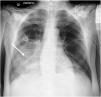

An anteroposterior chest radiography showed an area of lung consolidation in lower right lobe, indicating pneumonia (see Fig. 1). The lung ultrasound showed lobar consolidation, air bronchogram, pleural effusion and fibrin (see Fig. 2), as well as hyperechoic opacities that move centrifugally with respiration (dynamic air bronchogram) (see suppl. material 1). The patient was discharged alive after 2 months.